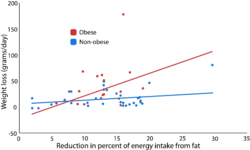

As in most science experiments, a good experiment using the diet-induced obesity model has an experimental and a control group. The control group is given a diet with low percentage of total energy from fat (e.g. 10%), while the experimental group is given a diet with a high percentage of total energy from fat (e.g. 60%).[4] The effect of the diet is quantified using the measures detailed below. Often, the experiment aims to see how obesity affects some other physiological or behavioral outcome, so other measures may be taken. Common such measures include stress (both physiological and psychological), changes in hormones, and insulin.[46]

Diets

Scientists have successfully induced obesity in animals using a wide range of diets. Although generally diets containing more than 30% of total energy from fat are considered to induce obesity, scientists have induced obesity with diets containing 13% to 85% of total energy from fat. The specific fatty foods used in the diets vary across studies, ranging from Crisco to lard to palm oil.[46] Other researchers have shown that an animal diet more similar to the human Western diet (i.e. a diet with high-fat, high-sugar, high-salt, and low-fiber content) is more effective in inducing obesity and obesity-related disorders than a traditional high-fat diet.[47]